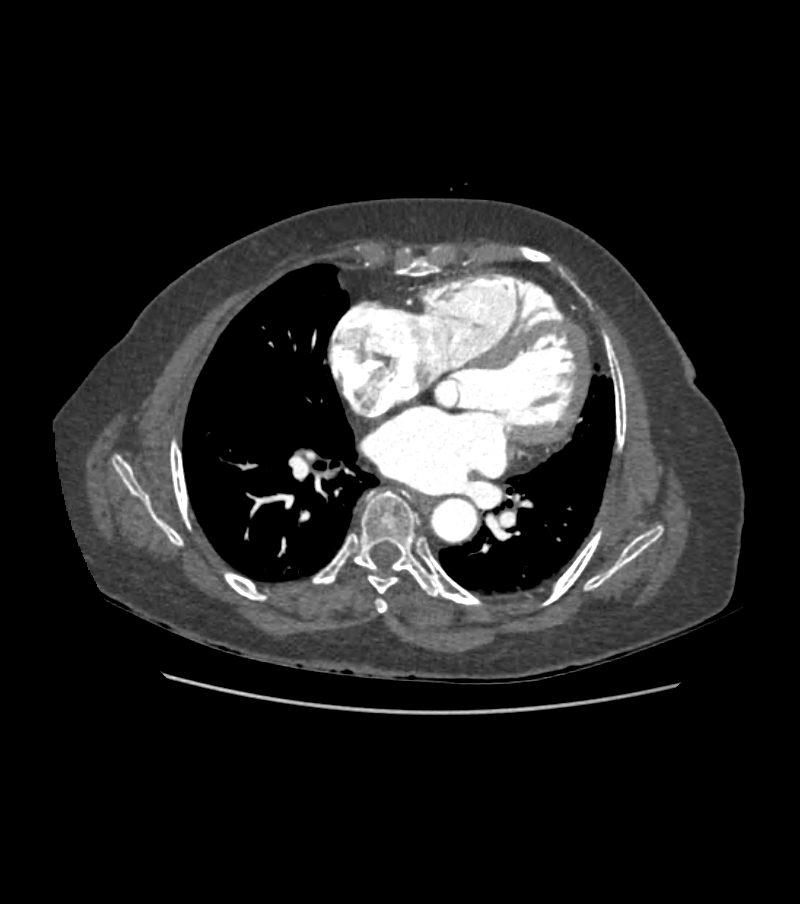

Les données sont obtenues par tomodensitométrie coronaire (CCTA), fournissant une visualisation détaillée de l’arbre coronaire en 3D.

La tomodensitométrie coronarienne (CCTA) couplée à l’estimation non invasive de la FFR par simulation numérique (FFRct) s’est imposée comme une alternative prometteuse. Les méthodes classiques de calcul reposent sur la dynamique des fluides computationnelle (CFD), qui modélise avec précision l’écoulement sanguin dans les artères coronaires. Cependant, ces approches CFD demandent un temps de calcul conséquent (de l’ordre de plusieurs dizaines de minutes à heures) et nécessitent des infrastructures informatiques lourdes, ce qui limite leur déploiement clinique en routine.